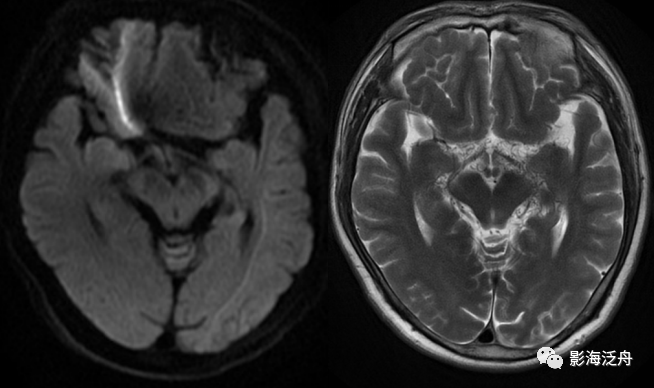

延髓左侧小梗死灶。这种斑点状的梗死灶漏诊也非常多见,患者症状一般不明显,我自己漏诊过两次。小的梗死灶多见于脑干、侧脑室周围,大脑皮层区一般不多见。因此,重点区域进行细致观察,可以减少此类疾病的漏诊。